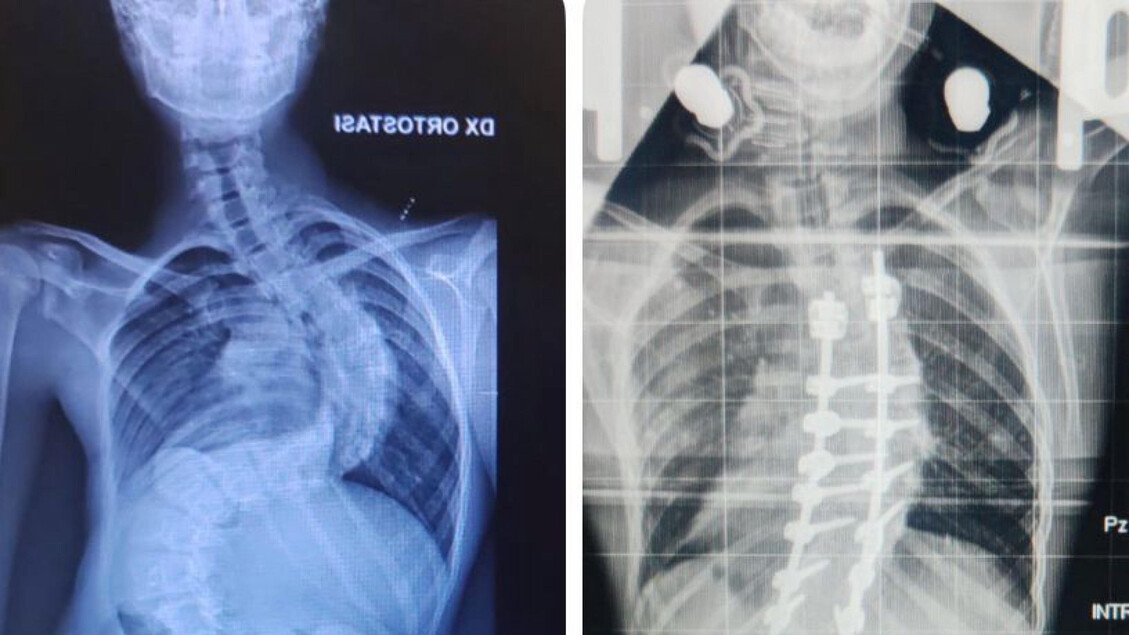

Francesco ha dovuto affrontare una preparazione preoperatoria meticolosa, che ha incluso l’uso di un dispositivo chiamato halo, utilizzato per la trazione continua della colonna vertebrale. Questo approccio ha permesso di ridurre la scoliosi da 117 a 45 gradi, un risultato straordinario che apre la strada a una vita normale per il giovane paziente.